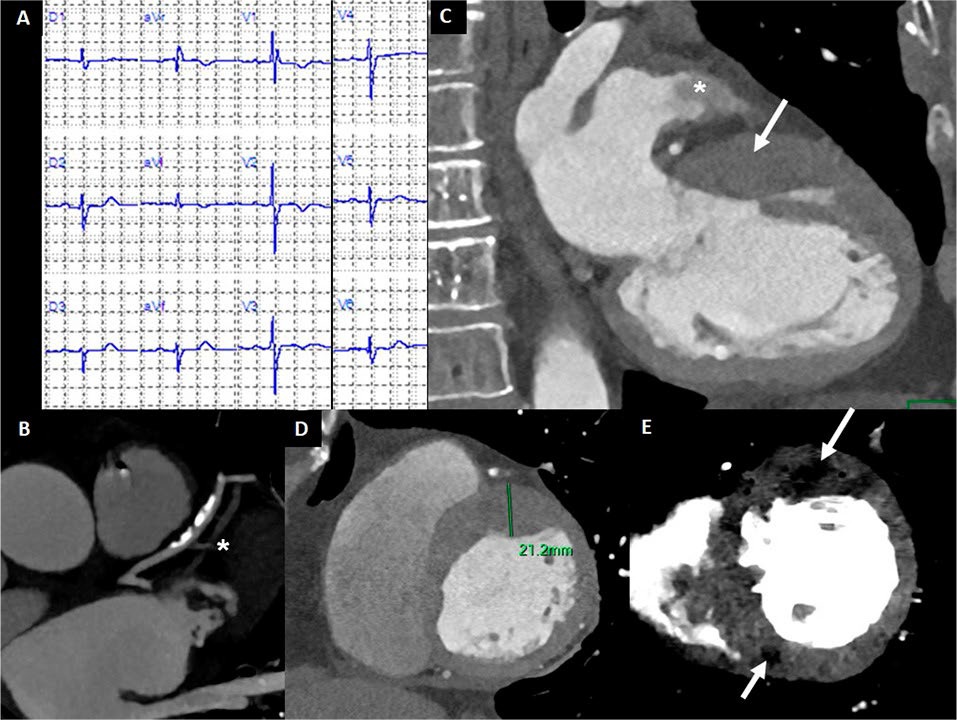

Evaluación fenotípica integral de la miocardiopatía hipertrófica mediante tomografía computada espectral